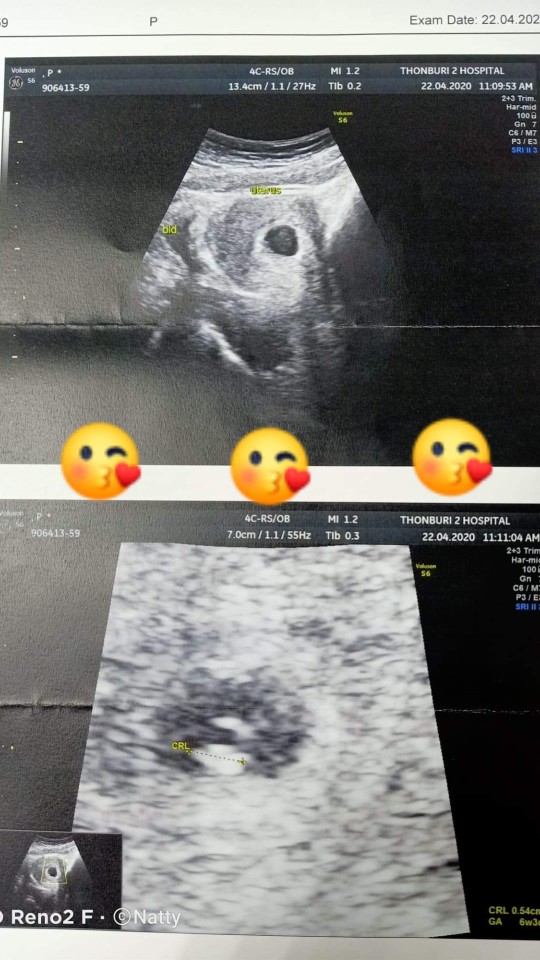

บ้านนี้20ธันวาจ้าา

บ้านนี้จ้าาา 18 ธ.ค.😍